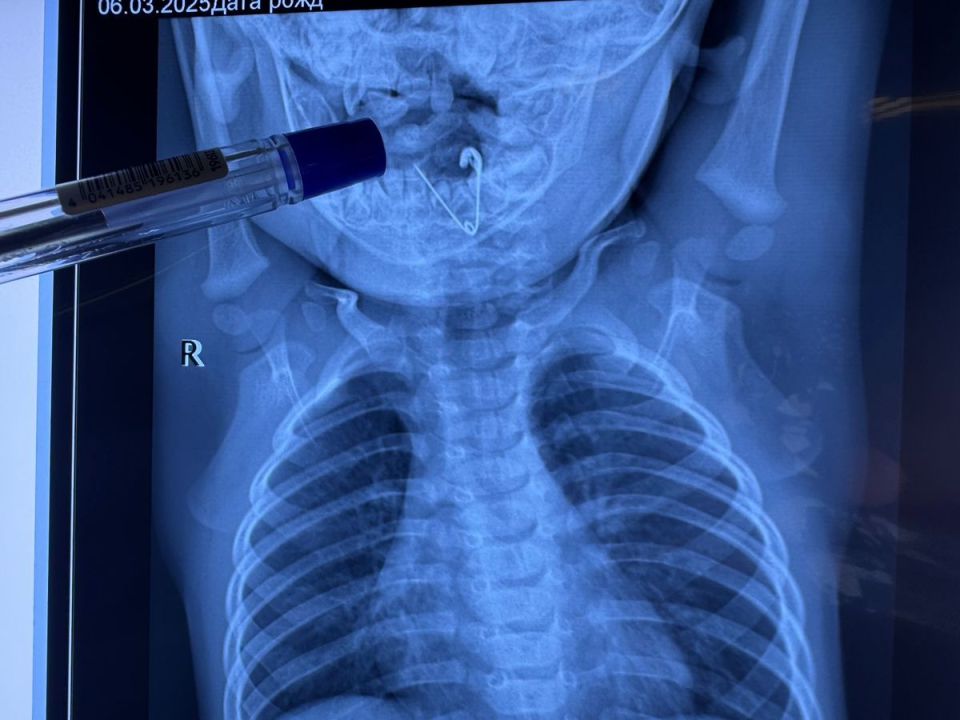

Врачи Краевой детской клинической больницы № 1 во Владивостоке извлекли из пищевода семимесячного мальчика открытую булавку. Опасный предмет был прикреплён к одеяльцу, с которого ребёнок его снял и отправил в рот.ПодробнееИсточник:...